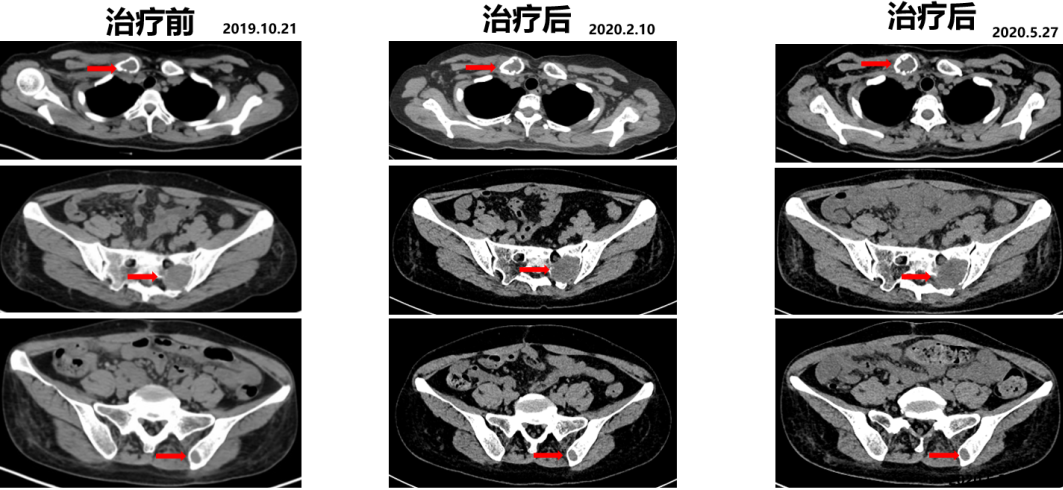

2019.10.21开始舒尼替尼50 mg po QD治疗(4/2方案)。

2020.05.27复查PET-CT病灶稳定,代谢较治疗前明显减低。影像学评估SD。

△舒尼替尼治疗后病灶稳定,代谢较治疗前明显减低